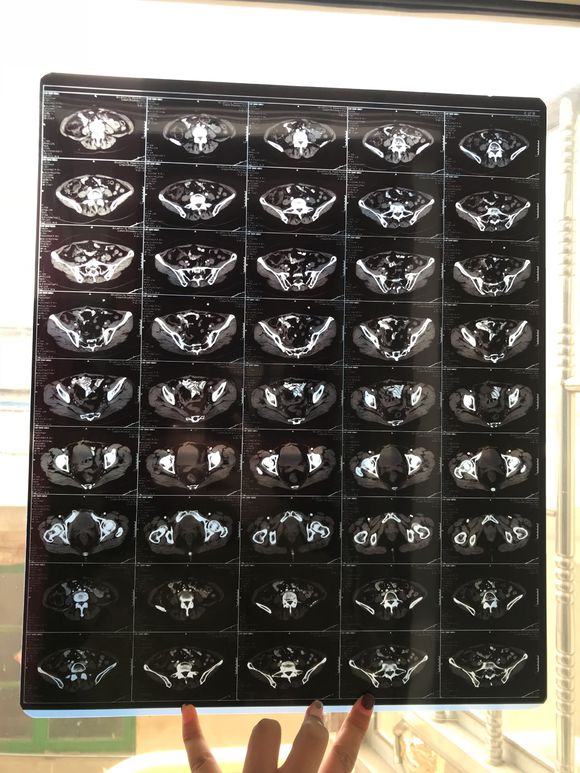

和你的故事 02019-04-09 患者家属我妈妈的病理结果报告,3期c1,大家可以帮忙看看吗,跪求了!我很急,谢谢!想知道是否严重,目前等术后出院后去肿瘤医院...